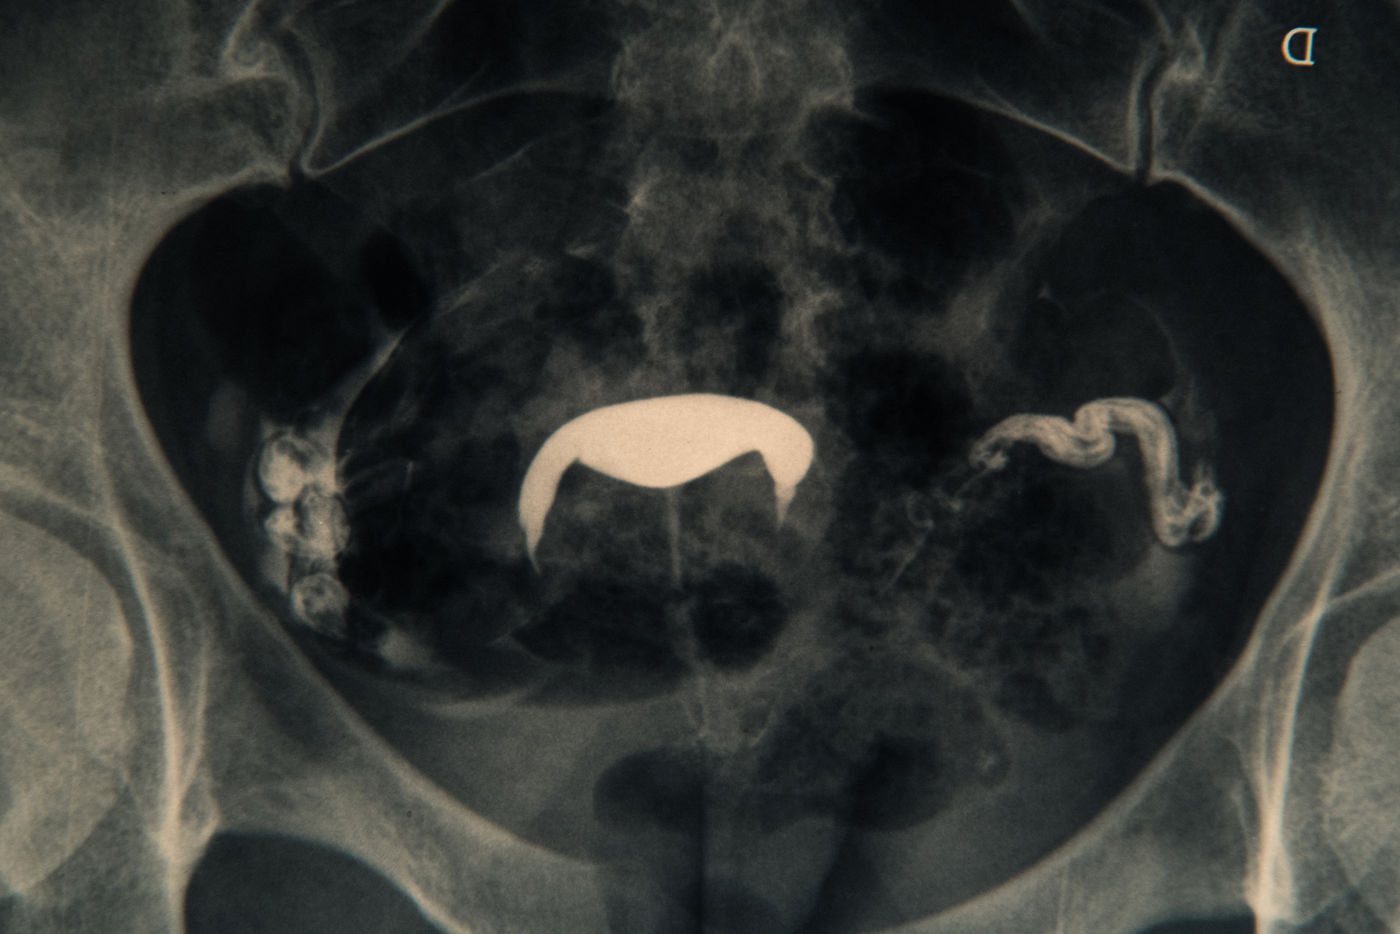

Il est question d'intimité, de non maternité et de mes ovocytes fraîchement congelés.

mon endométriose et d'une rupture il y a plusieurs années 1 mois avant une fiv.

It's about intimacy, non-pregnancy and my freshly frozen oocytes. My

endometriosis and a rupture several years ago 1 month before a ivf. T